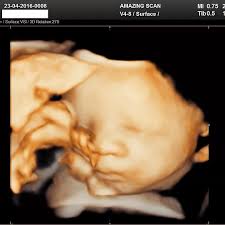

Doctors use medical scans to evaluate everything from head injuries to foot discomfort. Imaging technologies come in a variety of shapes and sizes. Each one functions in a unique way.

Some types of imaging tests use radiation. Others use sound waves, radio waves, or magnets. Learning about how medical scans work can help you feel more comfortable if you or a loved one needs one. It can also help you to know what to ask about before getting an imaging test.

For different disorders, several types of scans are used, and the sort of scan your doctor recommends will depend on your symptoms. Imaging scans are relatively safe and pose few hazards, but knowing what to expect will help you feel more prepared.